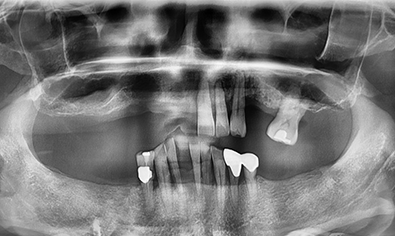

본래 내 치아처럼,

자연스러운 앞니 임플란트

임플란트의 안정성과 심미적인 부분을

모두 고려해야 하는 앞니 임플란트!

어금니보다 공간이 좁고 뼈가 얇기 때문에

정확한 각도와 방향으로 식립 되어야 합니다.

고난도 과정인 앞니 임플란트!

심미와 안정성 모두 약속드립니다.

정밀한 잇몸뼈 상태 확인

앞니 임플란트를 진행하려는 부위에 잇몸뼈가 퇴축되어 있다면 심미적인 문제가 발생할 수 있습니다. 이런 경우, 시술 전 잇몸뼈 이식 수술로 잇몸뼈를 보강한 후 임플란트를 진행해야 합니다.